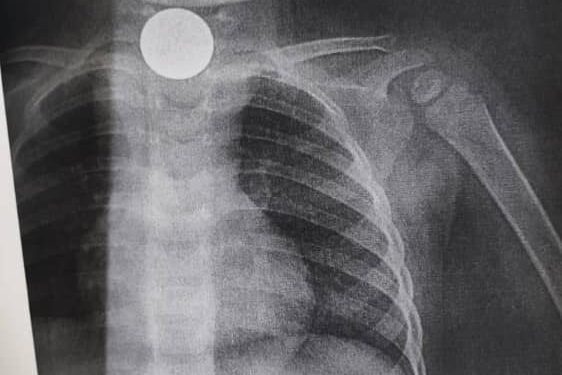

Кечээ, 8-сентябрда ооруканада бөтөн затты жутуп алган эки жаш эки айлык наристеге операция жасалган. Операцияны дарыгерлер Садык Кутбаев, Үмүт Пазылов, Данияр Масаев, анестезиологдор Давран Шакиров, Замирбек Кадыров жасашты.

Дарыгерлердин айтымында, наристенин кызыл өңгөчүнө туруп калган бөтөн зат эки ай бою билинбей жүргөн. Кээде гана жөтөлүп койгону болбосо, бир нерсе жутканынан кабар болгон эмес. Бөтөн зат кичинекей наристенин кызыл өңгөчүнүн капталына жабышып калган. Учурда баланын абалы жакшы.